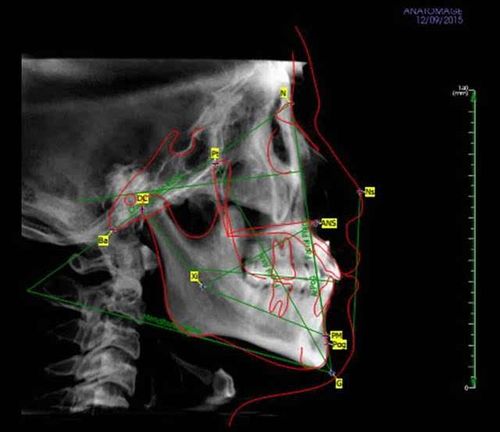

头颅侧位片正畸,正畸头颅侧位片

治疗前头颅侧位片,口内照 上:治疗前 下:治疗后患者基本满意,侧貌

头侧位片显示患者牙合型为安氏Ⅱ类,轻度骨性Ⅲ类,上前牙唇倾,均角.